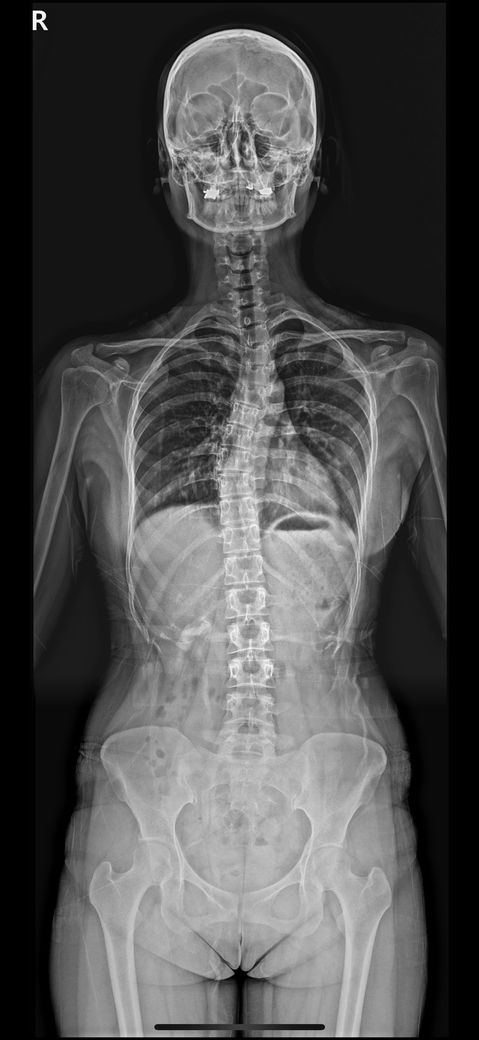

척추측만으로 인해 폐나 심장 압박 가능성

측만이있는 성인입니다.

고각도가 아니라 일단은 지내공 있는데

호흡이나 심장에 무리가 없는 엑스레이 맞나요?

숨이 잘차고 가슴이답답해요 측만때문이라 생각이들어요 전혀 그럴 가능성이 없는것인지요.

흉곽비대칭도 심한 편인가요?

측만은 꽤 됐고 각도 변화도 없는데 숨이 안쉬어지는 증상은 최근 4ㅡ5년 심해진거 같긴합니다. 한번 봐주시면 감사하겠습니다

측만증이 심한경우 장기를 압박하는경우도있긴하지만 흔하지는않습니다 사진상으로볼때 측만증이 있긴하지만 장기를 압박할정도까지는 아니기때문에 지속적으로 불편감이있다면 병원에서 검사와치료를받아보는것이 좋습니다

성인 척추측만증이라도 각도가 심하면 흉곽 변형으로 폐활량 감소나 심장 압박이 생길 수 있습니다 엑스레이만으로 폐 심장 기능 영향 여부를 정확히 판단하기는 어렵고 폐기능 검사 심장 초음파가 필요합니다.

최근 4~5년간 숨참과 가슴답답이 심해졌다면 다른 심폐 질환 가능성도 배제해야 합니다. 정형외과와 함께 호흡기 내과 진료를 받아 원인을 정확히 하는 것이 좋아요!

측만증이 호흡곤란을 유발하려면 심한 변형이 있어야 하는데, 올려주신 사진은 말씀드린 변형보다는 그 정도가 덜한 것으로 생각됩니다.

우선 측만증의 각도가 심하다면(보통 50도 이상) 폐와 심장을 압박하는 경우가 있지만 현재 고각도가 아니라고 진단 받으셨다면 걱정하지않으셔도 됩니다.

다만 측만증에 의해 흉곽 비대칭이 유발 될 수 있으며 정면 사진만으론 흉곽 비대칭을 확인하긴 어렵습니다.

우선 질문자님께서 불편함을 겪고 계신 숨이 잘차고 가슴이 답답한것은 충분히 측만증에 의해 나타날 수 있으니 가능성을 열어두는것이 좋습니다.

다만 지금과 같이 숨이 잘 차고 가슴이 답답한것은 심장 또는 폐와 같은 내과적인 문제일 수 있으니 흉부외과 또는 정형외과, 내과에 내원하셔서 필요한 과에 협진을 통해 치료를 받아보시길 추천드립니다.